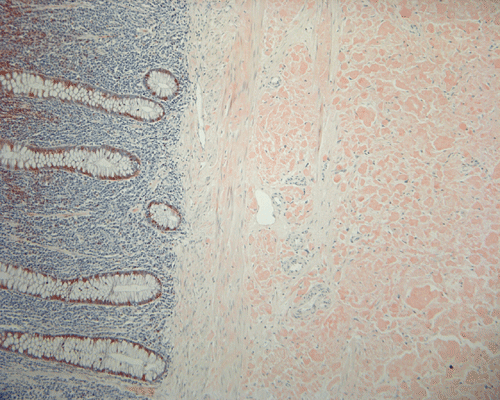

On low magnification, the mucosa appear intact and unremarkable. However, the submosa and muscular layer is replaced by a pale eosinophilic, hypocellular, amorphous material (Panel A). These material separate the smooth muscle bundles (Panel B and C). On Masson's trichrome, these material appears blue (Panel D). They are negative for elastic stain (Panel E). These material are stained orange by Congo Red stain (Panel  F and G) which gives an apple green birefrigence on polarized light (Panel H). Electron microscopy was performed and revealed non-branhing straight fibrils ranging from 6.6 to 8.3 nm in diameter consistent with amyloid.

Immunohistochemistry was performed and showed strong reactivity for lambda light chain. Numerous plasma cells within the mucosa overlying the amyloid deposition are also postive for lambda light chains. The results suggest a monoclonal lambda light chain plasma cell dyscrasia but it could not be further classified in the excised specimen.

Amyloid can be detected on routine hematoxylin and eosin (H&E) slides, all forms of amyloid deposits are amorphous and homogenous, with pale eosinophilic areas 15. Microscopic characterization of amyloid by special studies is necessary to confirm diagnosis of amyloidosis. Congo red histochemical stain remains gold standard for diagnosis and characterize by common to all amyloid aggregates orange or red color on light microscopy and clear apple-green birefringence under polarised light 1, 2. Most of the other stains available are not recommended to be used alone and are listed with decreasing specificity and sensitivity: Sirius red, thioflavine T, thioflavine S, toluidine blue, p-dimethylaminobenzaldehyde-nitrite, alcian blue, and crystal violet 15. Electron microscopy studies indicate that the basic assembled unit is a thin filament of about 4 nm in diameter, and that the mature fibrils consist of a few such proto-filaments aligned in parallel, often with a twist 2. Some other authors describe amyloid filaments under electron microscope as loose meshwork of 7–10 nm wide rigid, non-branching, hollow fibrils of indeterminate length. The fibrils measure from 30 to more than 1000 nm in length and are usually found in aggregates in extracellular spaces 15, 16.